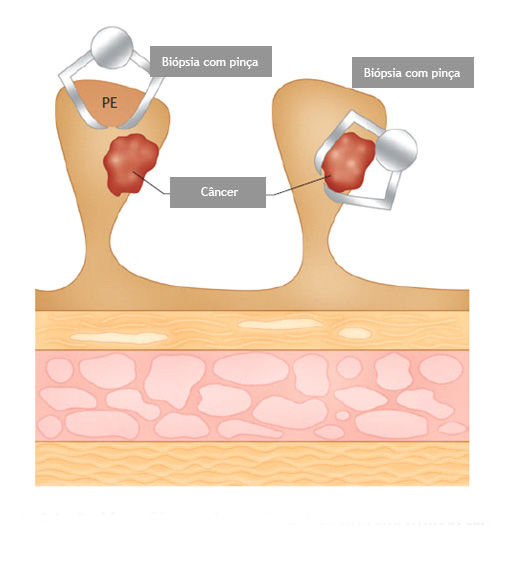

Por que apenas a biópsia de um pólipo não é suficiente?

Geralmente apenas uma região do pólipo é que se apresenta de forma cancerosa. Se for realizada uma simples biópsia do pólipo, a região cancerosa pode não ser atingida e o diagnóstico de câncer não ser realizado. Para se ter certeza do diagnóstico, o pólipo inteiro deve ser removido através do procedimento chamado de polipectomia.

O que é a polipectomia?

A polipectomia é a remoção completa de um pólipo permitindo assim o diagnóstico exato e muitas vezes a cura do próprio problema. Existem várias técnicas para a realização do procedimento que dependem do tamanho e do tipo de pólipo a ser ressecado.

Polipectomia com pinça

Pequenos pólipos podem ser removidos com segurança usando-se apenas uma pinça.

Polipectomia com alça diatérmica

Pólipos maiores necessitam ser removidos com alça e corrente de cauterização. Este procedimento permite cortar a base do pólipo e ao mesmo tempo coagular o local para evitar sangramentos.

Porém alguns pólipos possuem a base (pedículo) largo onde passam vasos calibrosos e por isto tem risco aumentado de sangramento na retirada mesmo usando a corrente de coagulação.